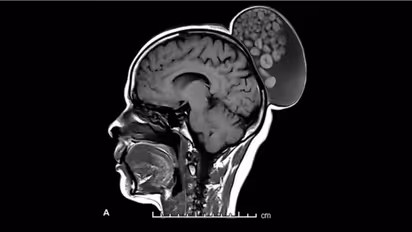

52 കാരിയായ സ്ത്രീ കുട്ടിക്കാലം മുതൽ തലയോട്ടിയിൽ മുഴയുമായി ജീവിച്ചു വരികയായിരുന്നു. എന്നാൽ ഇതുവരെ അവർ ചികിത്സ തേടിയിരുന്നില്ല. മുഴയിൽ നിന്ന് വേദന അനുഭവപ്പെട്ടിരുന്നില്ല. എന്നാൽ വീക്കം ഏകദേശം ആറ് ഇഞ്ച് നീളവും നാല് ഇഞ്ച് വീതിയിലും വളർന്നിരുന്നു. എംആർഐ സ്കാൻ ചെയ്തപ്പോഴാണ് തലയുടെ പിൻബാഗത്ത് മുടി കെട്ടി വച്ചതുപോലെ ബണ്ണിന്റെ വലിപ്പത്തിലുള്ള മുഴ കണ്ടെത്തിയത്. വെള്ളവും മുടിയും പ്രോട്ടീനായ കെരാറ്റിൻ ബോളുകളും നിറഞ്ഞ നിലയിലായിലായിരുന്നു നീക്കം ചെയ്ത മുഴ ഉണ്ടായിരുന്നതെന്നും ഡോക്ടർമാർ വിശദീകരിക്കുന്നു.

മുടിയുടെയും നഖങ്ങളുടെയും ചർമത്തിന്റെയും പുറംപാളികളിൽ സ്വാഭാവികമായി അടങ്ങിയിരിക്കുന്ന പ്രധാന പ്രോട്ടീനാണ് കെരാറ്റിൻ. ഇവയെ സംരക്ഷിക്കുന്നതിനും അവയെ ആരോഗ്യത്തോടെ നിലനിർത്തുന്നതിനും ഒരു ബാഹ്യ സംരക്ഷണവും ആന്തരിക ഘടനാപരമായ പ്രോട്ടീനും ആയി പ്രവർത്തിക്കുന്നു. ഇതിന്റെ വളർച്ച മൂലമുണ്ടാകുന്ന മുഴകളെ ഡെർമോയിഡ് സിസ്റ്റുകൾ എന്ന് വിളിക്കുന്നു, ഇത്തരത്തിൽ കോശങ്ങളിൽ നിന്ന് വളരുന്ന മുഴകൾ പലപ്പോഴും തലയിലും കഴുത്തിലും അടക്കമുള്ള ശരീര ഭാഗങ്ങളിൽ മുഴകളായി പ്രത്യക്ഷപ്പെടാറുണ്ട്. ഇത്തരം മുഴകളുടെ വികാസത്തിന്റെ കൃത്യമായ കാരണം വ്യക്തമല്ലെങ്കിലും, അവ പൊതുവെ നിരുപദ്രവകരവും വേദന രഹിതവും ആണെന്നാണ് ഡോക്ടർമാർ വിലിയിരുത്തുന്നത്. എന്നാൽ, ചില ഘട്ടങ്ങളിൽ അവ അണുബാധകളും, അടുത്തുള്ള എല്ലുകൾക്ക് കേടുപാടുകളും ഉണ്ടാക്കുന്നതിലേക്ക് നയിച്ചേക്കാം.